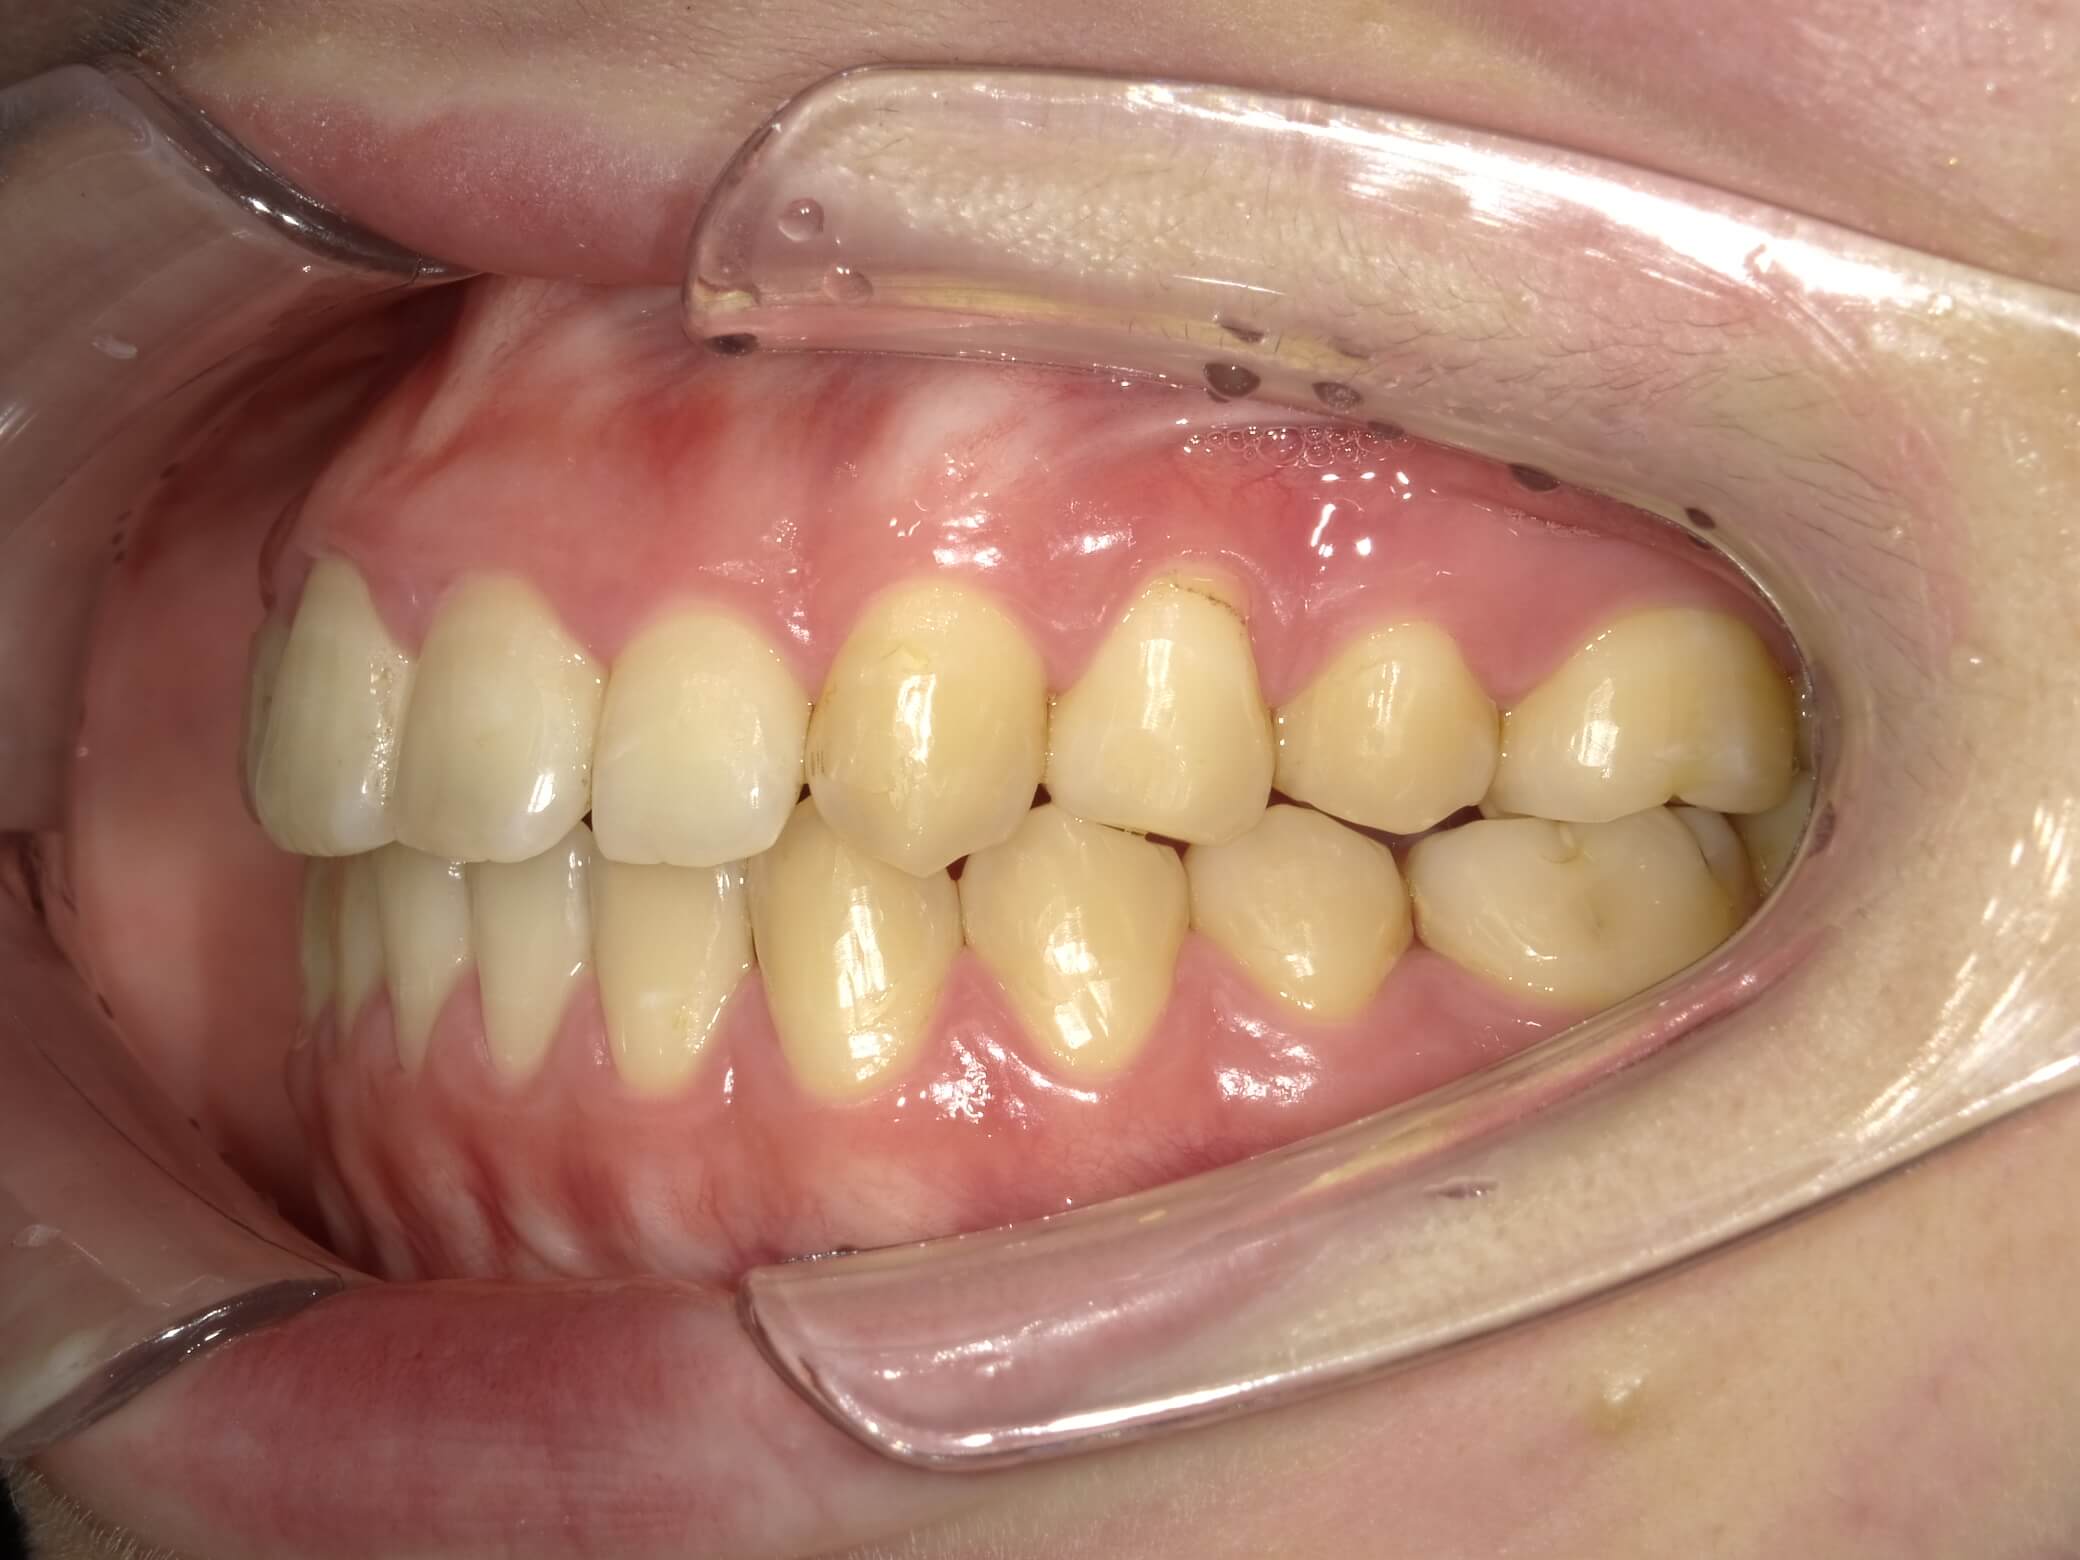

• 治療前